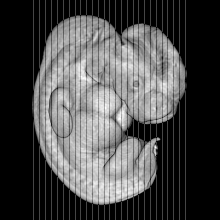

Carnegie Stage 17 (41 post-ovulatory days)

Most embryos at stage 17 are approximately 41 postovulatory days old and measure 11-14 mm in length. Distinguishing criteria for this stage include distinct digital rays in the hand plate, a rounded digital plate in the foot, a complete complement of hillocks on the mandibular and hyoid arches, distinct nasofrontal grooves, and a slight indication of a lumbar curvature.

This specimen does not represent normal development. The caudal nueral tube has failed to close properly.

MRI Slice Selector

Mouse: click on a line below to select a view

Finger: tap a line below with a very light touch